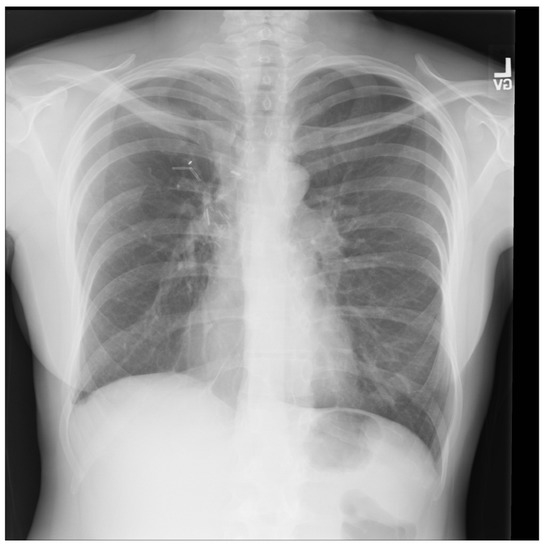

For a more intuitive understanding, we visualize a sample of each category in Figure 9, Figure 10 and Figure 11.

Figure 11. Normal sample: X-ray Image dataset.